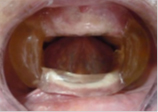

| Management of Obstructive Sleep Apnea in an Edentulous Lower Jaw Patient with a Mandibular Advancement Device [17] | 1. Simplicidad en el diseño 2. Fácil fabricación 3. No aumenta la dimensión vertical 4. Económico por su fabricación | 1. Monobloque 2. En pacientes con limitada apertura es de difícil inserción 3. No permite movimientos de lateralidad 4. Excesiva rigidez | 1. Aumentar el espacio entre la base de la lengua y la pared posterior de la faringe. 2. Ubicar en posición adelantada la mandíbula | ![]() |

Nayar y Knox [17], en el 2005, propusieron un aparato para el tratamiento de la AOS en edéntulos totales, donde el diseño incluyó una férula convencional maxilar realizada al vacío y una férula de avance mandibular, ambas soportadas por el tejido blando del paciente y unidas entre sí por acrílico autopolimerizable. La principal limitante de este dispositivo es que se dependía de la expansión de los flancos linguales que presentaba el paciente para lograr una retención adecuada.